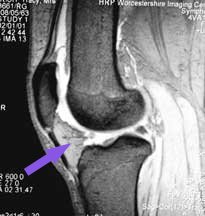

From the point of view of arthroscopy, it is important to know that the joint cavity extends upwards, a handsbreadth above the patella, into a pocket called the 'suprapatellar pouch' - literally 'the pouch above the patella'. You can see this pocket in these MRI scans (white colour in this view). Surgeons often fail to fully examine this area, particularly with the arthroscope above the patella, and problems can be missed.